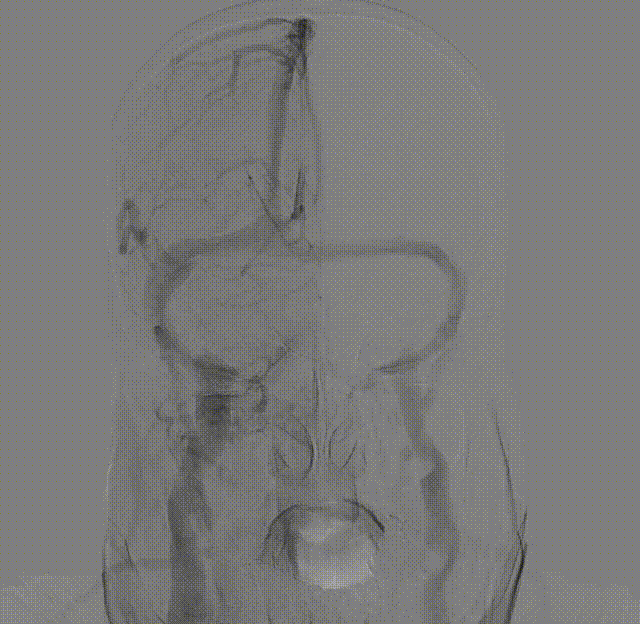

患者取平卧位置,常规消毒、铺巾和局麻右侧腹股沟下穿刺点后,穿刺置入5F动脉鞘,再以5F单弯行选择性脑动脉造影。造影示:II型主动脉弓,右侧颈内动脉C1段重度狭窄。

左侧颈动脉未见明显异常。

造影显示左侧椎动脉V1段中重度狭窄。

使用雅培Workhorse保护伞导丝先行通过病变狭窄处,随后将Emboshield Nav6保护伞沿导丝推送经过C1端弯曲处。借助Nav6保护伞的支撑,推送6F 115cm中间导管至C1远端,利用特洛伊木马技术将Nav6保护伞输送并放置于颈内动脉C1段。回撤中间导管,在透视状态下释放Nav6保护伞,Nav6圆周骨架在透视下显影清晰,定位准确。

将中间导管撤至颈总动脉,通过Workhorse导丝送入4mm*20mm球囊至右侧颈内动脉狭窄病变处,准确定位后以适当压力预扩狭窄病变,造影示狭窄改善不明显。撤出球囊,再次通过Workhorse导丝送入5mm*30mm球囊至狭窄病变处进行扩张,造影提示狭窄稍改善。

考虑到靶血管较迂曲,拟使用中间导管进行支架释放。在Workhorse导丝引导下,将中间导管通过迂曲段,经由中间导管送入8mm*40mm颈动脉支架至右侧颈内动脉狭窄处。回撤中间导管至颈总动脉后,在透视状态下准确释放支架。

造影显示残余狭窄小于30%,未进行后扩张。术后造影显示狭窄解除,支架置入部位满意,血流较术前明显改善。使用中间导管将Nav6保护伞顺利回收后,对股动脉穿刺点进行止血,患者安返病房。